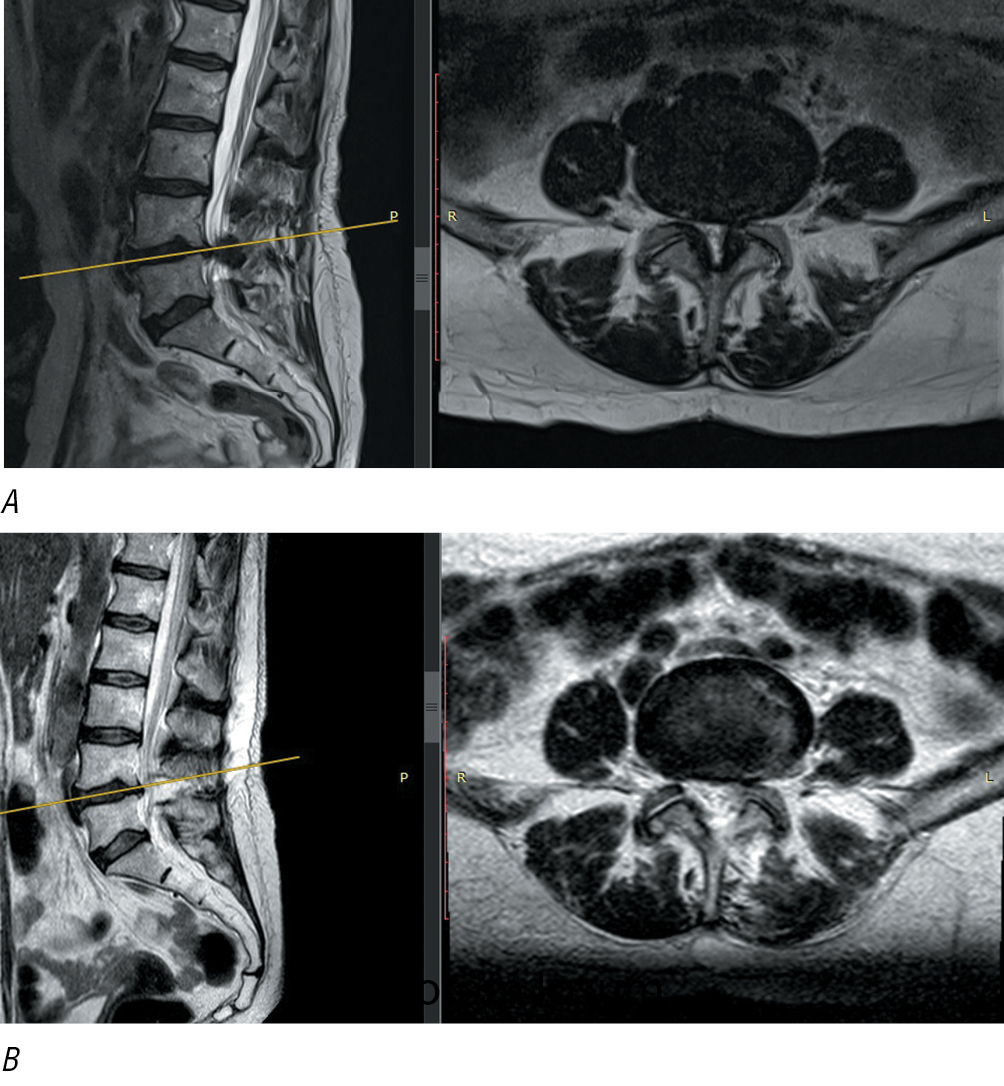

Magnetic resonance imaging (MRI) is a method of choice for diagnosing degenerative spinal stenosis. Fig. 1 shows visual grading of stenosis according to С. Schizas [11]. Significant stenotic changes on computed tomography or MRI in healthy people without complaints is a challenge related to imaging [12]. Therefore, significance of any imaging results in patients with SC stenosis is defined by their clinical findings.

Fig. 1. Visual grading of stenosis according to С. Schizas [11].